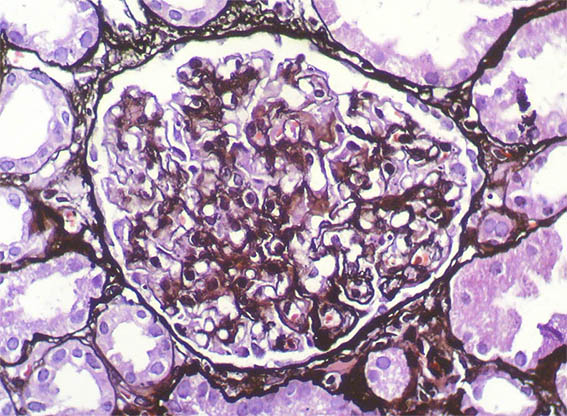

A 25-year-old woman with no relevant history is evaluated for presenting 3 months of evolution of constitutional symptoms, disseminated skin lesions with vasculitis-like appearance, polyarthritis affecting small and medium joints, anemia, acute phase reactants elevation, lymphopenia, hypocomplementemia C3 and C4, uroanalysis with active sediment and subnephrotic proteinuria: 1.8 g/24h; Cr; 1.1 mg/dL, BUN: 18 mg/dL. ANAs and anti-DNA positive at high titers, anti-RNP positive, VDRL falsely positive. Anticardiolipin and lupus anticoagulant: negative, other markers for APS: Negative.

See the images of the renal biopsy.

Figure 5. Methenamine-silver, X400.